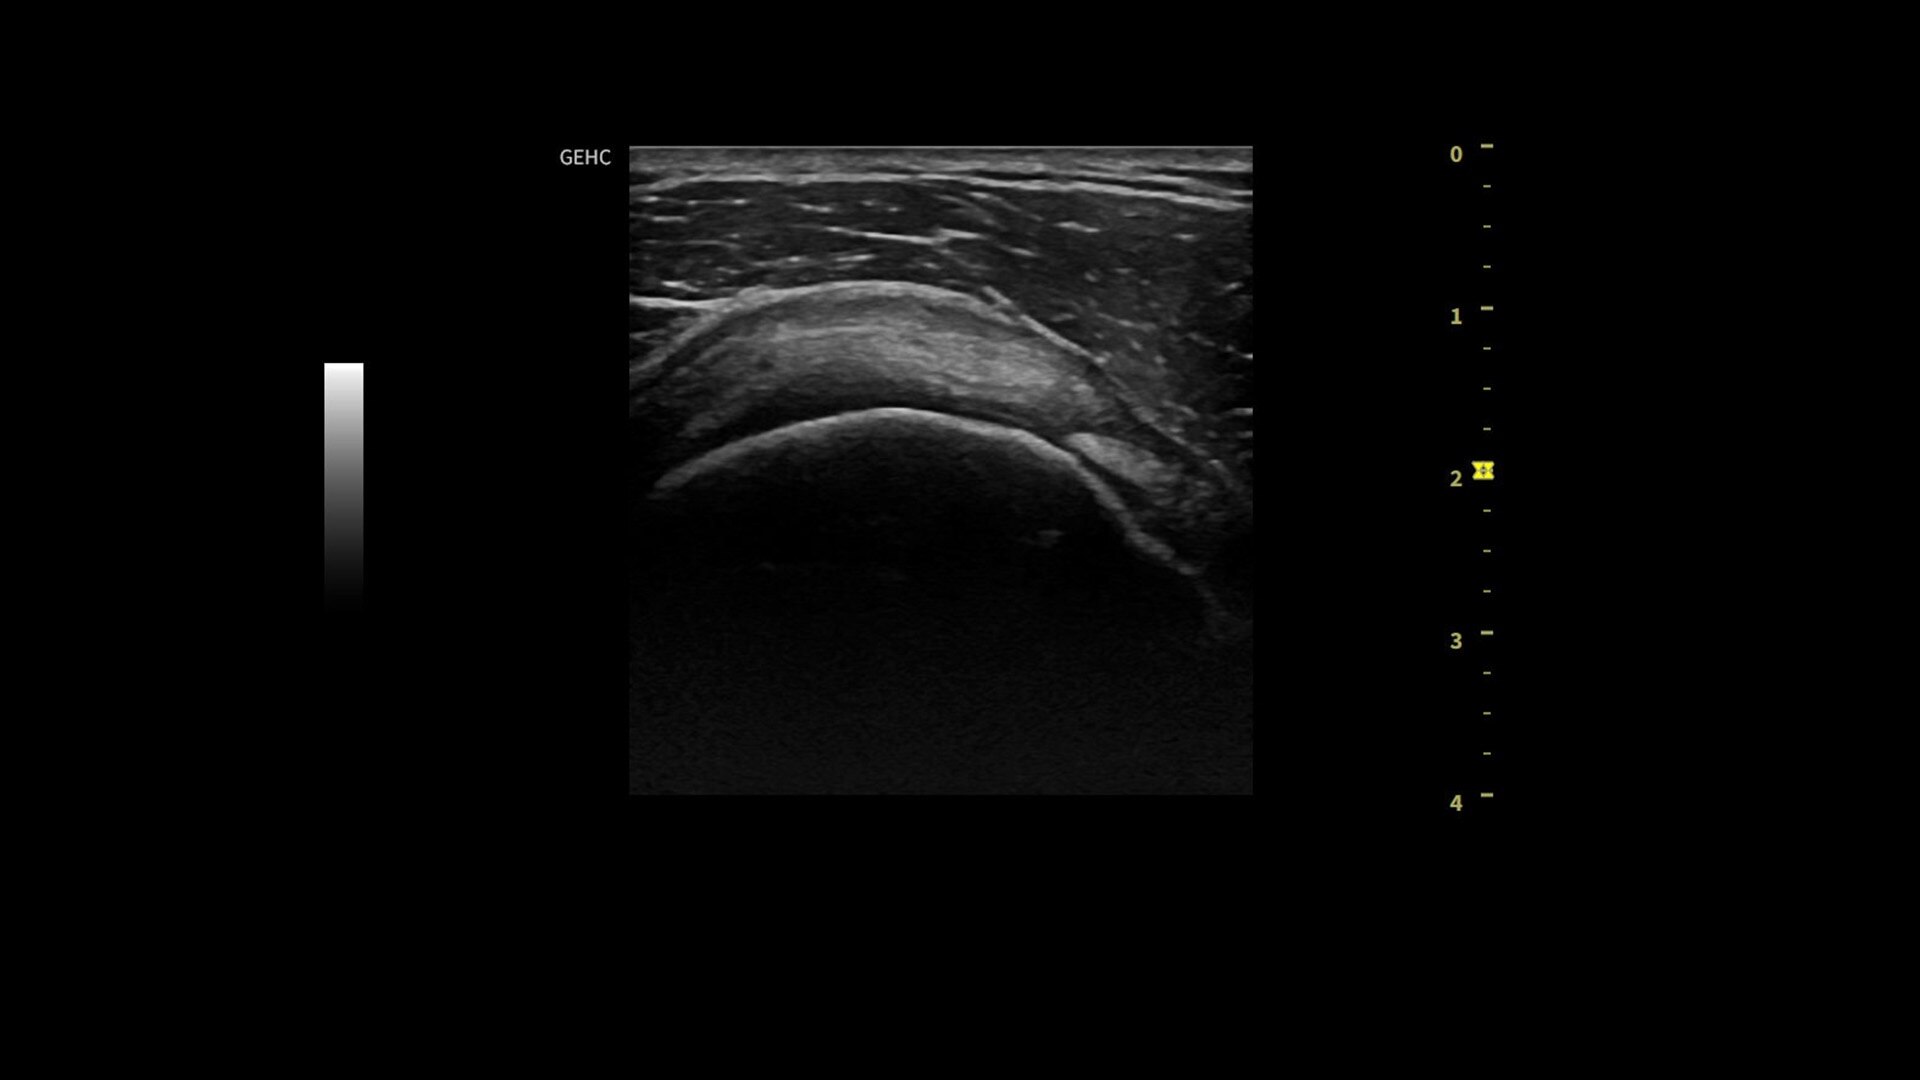

Powered by VisionBoost Architecture, Versana Premier provides optimal image quality so users can easily reach a diagnosis. Advanced clinical features help address challenging cases while automated tools help reduce scan time:

• Optimize images while scanning with Whizz clinical features, easily improve Color Doppler with Whizz Color Flow, and view scans in the image style that suits your preference with Whizz Easy Style